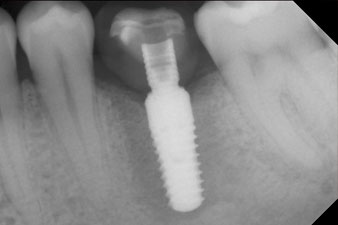

El torque en el momento de la carga mecánica fue de 43 Ncm. Asimismo, después de atornillar un poste de medición especial adaptado al sistema de implante (SmartPeg), el valor ISQ se determinó con la sonda del módulo Osstell ISQ de W&H.

Este módulo Osstell ISQ que se encuentra disponible como accesorio para la unidad Implantmed de W&H y se acopla al motor de implantes (véase figura 11). El valor ISQ adimensional fue de 64 justo en el momento de la inserción en la dirección bucovestibular y de 68 en la dirección mesiodistal (valor máximo = 100).

Después de la cicatrización de los tejidos blandos, se volvió a determinar la estabilidad del implante antes de continuar con el tratamiento protésico.

Los dos valores eran prácticamente idénticos y se encontraban en la transición del área media a la alta; en este punto cabe reseñar que el valor más bajo sirve siempre como referencia para establecer el tratamiento adecuado.

Con ello, fue posible documentar una correcta osteointegración y una estabilidad biológica suficiente, lo que permitió realizar una conformación en la misma sesión.

Las figuras finales muestran la corona de composite monolítica atornillada in situ y la radiografía de control (figuras 9 y 10) (6).